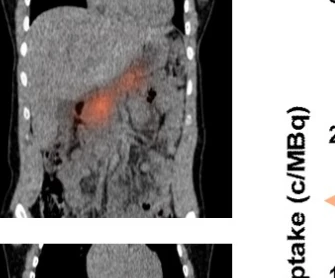

來自荷蘭拉德布德大學(Radboud University)研究團隊采用了單光子發射計算機斷層掃描(SPECT)這種非侵入性核成像技術,來檢測胰腺對示蹤劑111In-exendin的吸收,這種示蹤劑可以靶向在β細胞上大量表達的GLP-1受體,從而檢測胰腺中仍然存留的β細胞。在非糖尿病人群體內,GLP-1受體與腸道分泌的多肽類激素GLP-1相結合,可以刺激胰島素的分泌,并且抑制胰高血糖素的分泌,從而促進血糖的新陳代謝。

研究中,10名年齡在21-54歲、平均確診11年的1型糖尿病患者進行了上述影像檢查。此外,還對10名年齡和性別相匹配的健康對照受試者進行了同樣的檢查。

結果顯示,在10名1型糖尿病患者中,6個人體內測量到了胰腺對111In-exendin的吸收——也就是說,體內很可能仍然有β細胞。更令人驚訝的是,有5名1型糖尿病患者的胰腺示蹤劑吸收量與健康對照組中較低的胰腺示蹤劑吸收水平相似。這意味著,即使患病多年的1型糖尿病患者中,如果有足夠的治療方法,這些殘留的β細胞功能有可能被恢復。